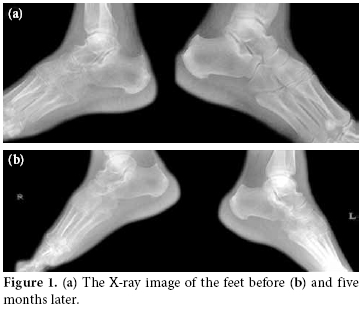

The patient had already been diagnosed with AS according to the modified New York criteria. She had bilateral sacroiliitis, lumbar motion restriction, morning stiffness, and enthesitis. Laboratory examination showed a high erythrocyte sedimentation rate (ESR) (65 mm/h) and C-reactive protein (CRP) (20 mg/dl) along with a Bath Ankylosing Spondylitis Disease Activity Index (BASDAI) of 5.1. Her earlier magnetic resonance imaging (MRI) and bone scanning were compatible with sacroiliitis and enthesopathies. Therefore, we looked for an AS-related pathology. She had bilateral ankle synovitis in ultrasonography, but an MRI revealed little synovitis and/or tenosynovitis in the right ankle. It showed periarticular and periosseous edema. An X-ray showed one-sided diffuse osteoporosis (figure 1a). Three-phase bone scanning showed diffuse increased uptake on delayed phase in the right foot which is consistent with CRPS1. Her clinical picture met the criteria for CRPS1 according to the Kozin criteria.[6] Otherwise, her general clinical picture was compatible with active AS.

Three weeks later, the patient was able to walk more than five minutes without pain. Her dermis was nearly normal, and she had no pain. She was able to perform her daily activities freely and felt much better with the decrease in inflammatory activity of AS. Acute phase reactants had returned to normal ranges. Her sleeping quality had increased, and her morning stiffness had decreased significantly. A bone scan showed no pathology. A control X-Ray did not show the diffuse osteoporosis (figure 1b).